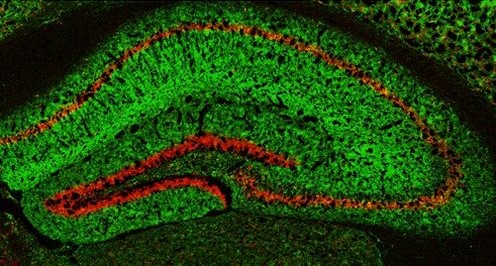

Под Новый год кто-то с друзьями ходит в баню, а Лондонский Фонд медицинских исследований проводит конкурс праздничных изображений. В прошлом году мы уже писали о победителе 2022 года (см. картинку дня Вирусные снежинки). Канун Нового года — повод вспомнить о том, как прошел год, и поговорить об изображении, занявшем почетное второе место в 2024 году. На созданной учеными из Эксетерского университета открытке мы видим срезы гиппокампа мыши — участка мозга, играющего важную роль в формировании и организации воспоминаний. Именно эта структура помогает нам удерживать в памяти важные моменты уходящего года. Чтобы получить такой снимок, ученые применили флуоресцентные красители, которые подсвечивают определенные белки в ткани мозга. Здесь отчетливо видны слои и изогнутая форма гиппокампа, напомнившая ученым ветвь новогодней ели. Они размножили и скомпоновали эту «ветвь», создав праздничное дерево.

На заглавном изображении мы видим четкую дугу гранулярных клеток зубчатой извилины, или stratum granulosum, а также компактный слой пирамидных клеток гиппокампа — stratum pyramidale, представленные в несколько непривычной ориентации, так как гиппокамп развернут на 180 градусов по сравнению с традиционными изображениями. Эти структуры выделены фиолетовым цветом, образуя четкие, плотные полосы.

В данном случае в качестве такой мишени мог выступать, например, NeuN — белок, широко используемый в качестве биомаркера нейронов. Сам по себе NeuN не светится, но к нему можно подобрать молекулу-«посредника», специальное антитело, которое узнает именно этот белок и прочно с ним связывается. К антителу, в свою очередь, может быть присоединен флуоресцентный краситель. При освещении такого образца под флуоресцентным микроскопом можно выявлять слои тел нейронов, такие как гранулярный слой зубчатой извилины и пирамидный слой гиппокампа. Хотя эти слои хорошо различимы даже на классических гистологических срезах, при флуоресцентной микроскопии они выглядят как яркие линии. Зеленые участки заглавного изображения соответствуют слоям гиппокампа, где почти нет тел нейронов, но сосредоточено огромное количество их отростков — дендритов и аксонов, а также мест контакта между клетками — синапсов. В качестве мишени в этом случае могли выступать белки, связанные с дендритами, например MAP2 — белок, ассоциированный с микротрубочками дендритов. Как и NeuN, он сам по себе не флуоресцирует, но может быть обнаружен с помощью специфических антител, несущих флуоресцентную метку. Таким образом, комбинация меток NeuN и MAP2 могла превратить аккуратно расставленные срезы гиппокампа в «дендритную» новогоднюю ёлку со светящейся фиолетовым цветом гирляндой из нейронов (какие именно белки визуализированы на открытке, авторы не указали). А для завершения композиции ученые добавили художественные элементы — декоративное основание и звезду на вершине.

Гиппокамп мыши, окрашенный по MAP2 (дендриты, зеленый) и NeuN (тела нейронов, красный). Изображение с сайта thermofisher.com

Фото © Dr Nicholas Clifton, Kamile Tamusauskaite с сайта medicalresearchfoundation.org.uk.